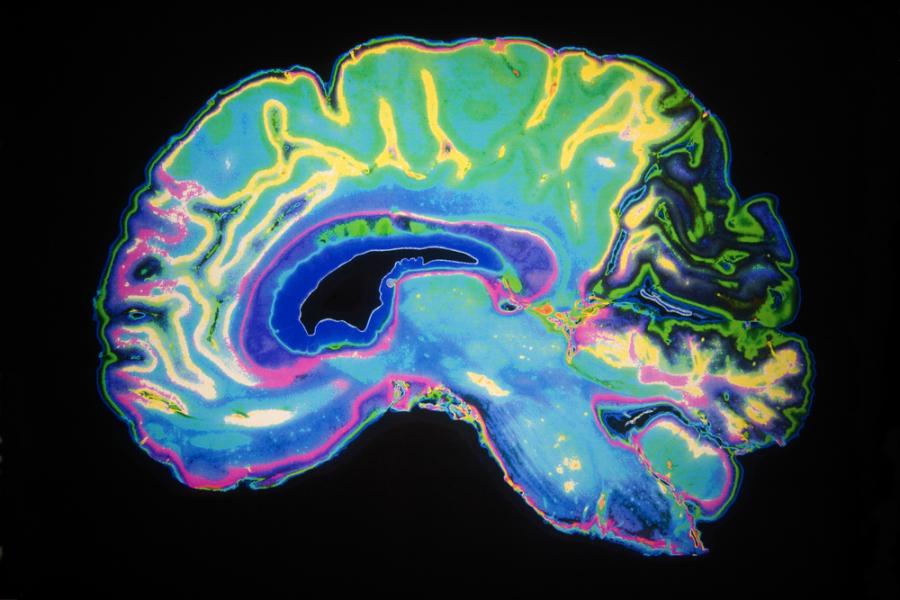

Болните, страдащи от заболяването, изпитват най-различни неврологични симптоми, измежду които загуба на памет, проблеми със зрението и съня, промени в поведението, необяснима болка, халюцинации, проблеми с координацията и силни мускулни болки.

Д-р Ръсел отбелязва, че на пръв поглед симптомите наподобяват болестта на Кройцфелд-Якоб - рядко и фатално заболяване на мозъка, предизвикано от приони - необикновен вид инфекциозен агент, който се състои само от белтък. Прионите са ненормално-структурирани (пространствено нагънати) форми на белтъците на организма-хазяин, които са способни да преобразуват структурата на нормалните белтъчни молекули в подобна на своята ненормална структура. Някои заболявания от този тип могат да се прихванат след консумацията на мозъчна тъкан на заразен индивид или животно. Съществуват и няколко необикновени случая на хора, които са се заразили с това заболяване, след като са яли заразена тъкан (като например мозъци на катерица).

Направените лабораторни тестове обаче отхвърлят болестта на Кройцфелд-Якоб, както впрочем и всички останали известни прионни болести, като потенциална възможност. Това означава, че или става дума за ново прионно заболяване, или за напълно ново състояние.